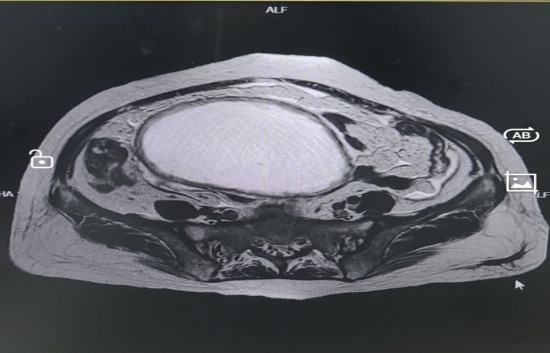

入院检查发现曾阿姨腹部隆起,经过相关检查和多学科联合会诊讨论后,认为曾阿姨腹部巨大包块为肿瘤合并感染可能性大,伴有明显邻近器官压迫症状,手术指征明确。经过与患者及家属充分沟通后,在全麻下行剖腹探查术,术中发现巨大包块来源于左侧卵巢,与肠管粘连致密,包块内可见大量黏液及脓液流出,遂行经腹全子宫切除术+双侧输卵管卵巢切除术+肠粘连松解术+腹腔粘连松解术+阑尾切除术,术后恢复良好出院。术后病理提示左侧附件黏液性肿瘤,阑尾低级别黏液性肿瘤,二者同源。